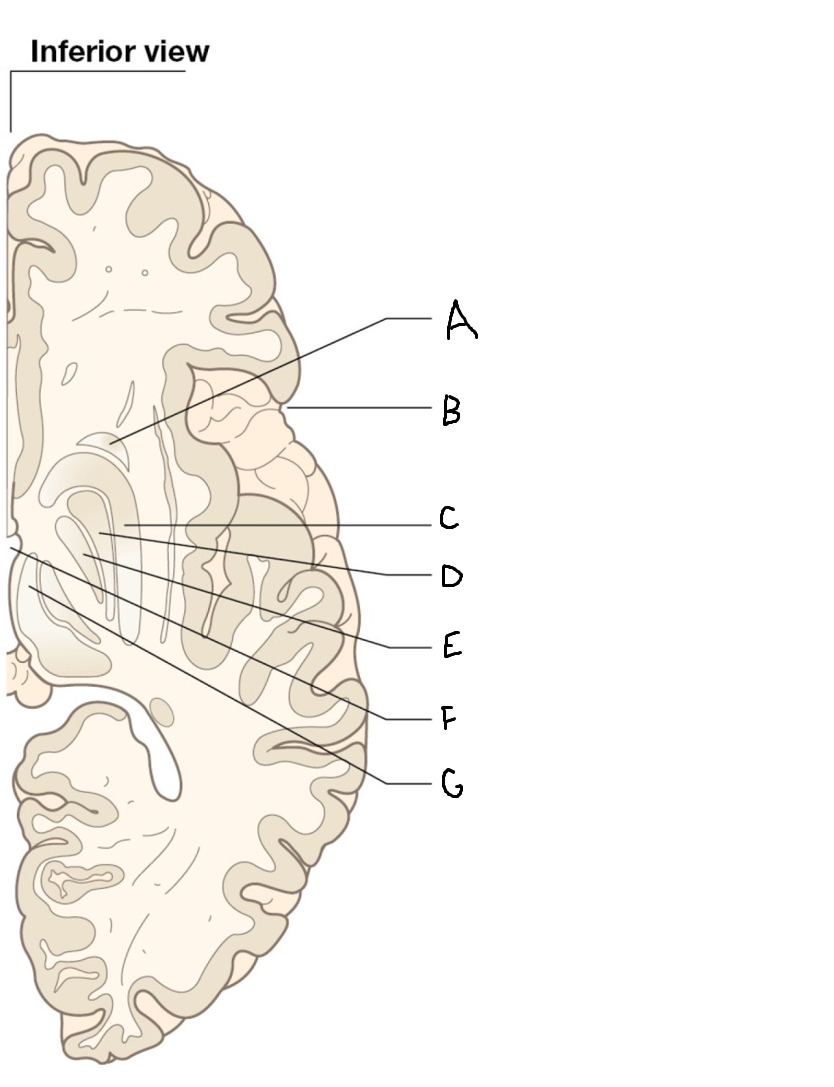

A

internal capsule (anterior limb)

B

caudate nucleus body

C

caudate nucleus head

D

putamen

E

caudate nucleus tail

F

thalamus

G

internal capsule (posterior limb)